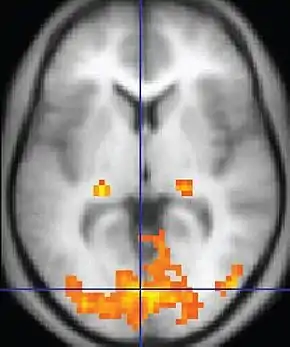

Functional MRI (fMRI)Blood-oxygen-level dependent imagingBOLDChanges in oxygen saturation-dependent magnetism of hemoglobin reflects tissue activity.[70] Localizing highly active brain areas before surgery, also used in research of cognition.[71]